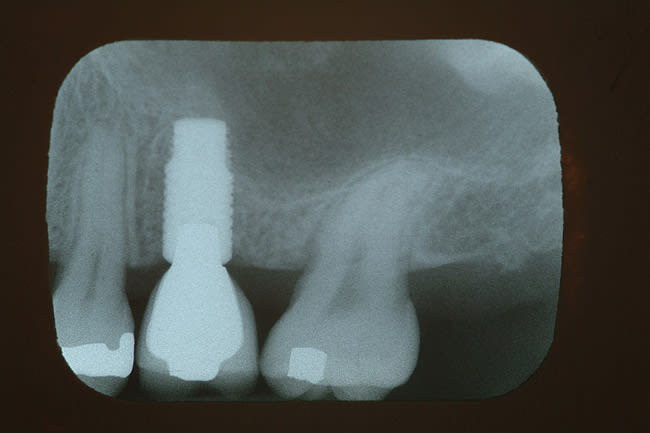

A 39-year-old woman was seen for evaluation, wanting her recently fractured upper left second bicuspid (x-ray pictured in Figure 1) repaired. She reported a prior dental history of an abscess that had developed under a large silver filling and, to resolve the problem, she had undergone endodontic treatment and had a traditional porcelain-fused-to-metal (PFM) crown put in. She was chewing on an almond when the tooth cracked and the crown came off. Clinical examination suggested that the root was too short to lengthen surgically. It was decided to remove the tooth and place a dental implant. The extraction site did not require bone grafting to maintain the width of the ridge.

A 4.3-mm diameter Hiossen implant (www.hiossen.com) was placed and maximum torque of 60 newton centimeters was achieved. The implant used in this case had microthreads on the top quarter of the implant and the abutments placed were narrower than the head of the implant. This relationship of decreased abutment/implant diameter is described as platform switching. The implant was fully integrated and uncovered in 4 months, with a temporary abutment placed (Figure 2). With an internal connection design—which can create an optimal condition for the preservation of crestal bone—providing a more rigid connection from a mechanical standpoint,10 the implant was restored using a traditional PFM crown, which established optimal emergence profile. Figure 3 shows the crown in place for 18 months, with no tissue inflammation.